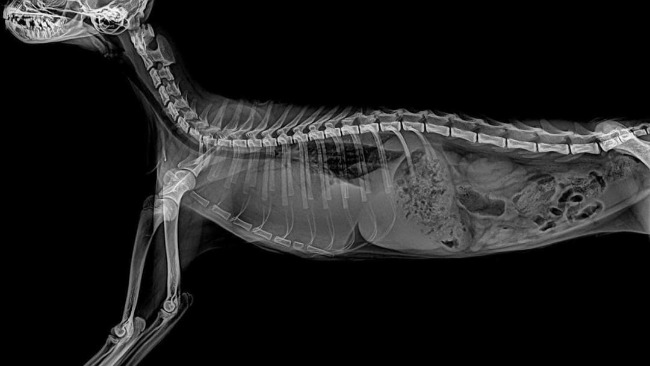

Zaniepokojeni, udaliśmy się z Mikim do weterynarza, gdzie przeprowadzono szereg badań. Diagnoza była druzgocąca – zakaźne zapalenie otrzewnej, znane jako FIP (zapalenie otrzewnej), w brzuszku Mikkiego zbiera się płyn. Miki ma duże szanse pod warunkiem szybkiej reakcji i podjęcia odpowiedniego leczenia.